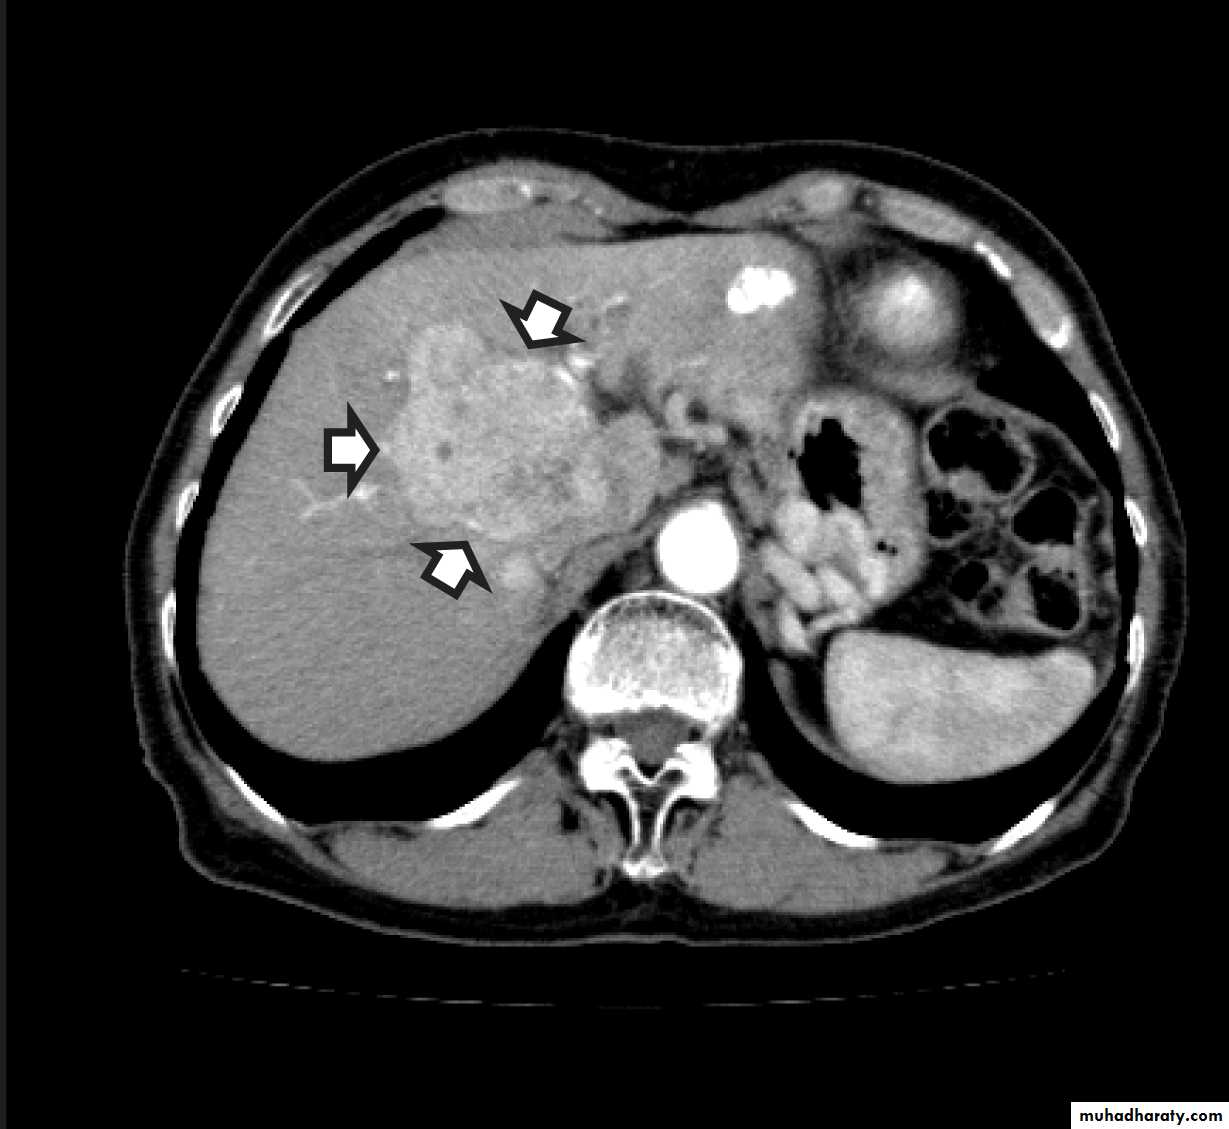

CT scan

Malignant neoplasms:

hepatocellular carcinoma